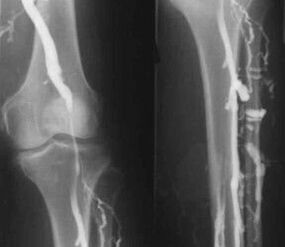

Ένας έμπειρος φλεβολόγος μπορεί να προσδιορίσει την παρουσία κιρσών στις εν τω βάθει φλέβες των κάτω άκρων από τα χαρακτηριστικά συμπτώματα, τα οποία είναι επίσης ευδιάκριτα σε μια φωτογραφία των ποδιών. Ωστόσο, οι μέθοδοι θεραπείας της νόσου επιλέγονται μεμονωμένα μετά από λεπτομερή εξέταση του ασθενούς και λαμβάνοντας υπόψη όλα τα επιμέρους χαρακτηριστικά του σώματός του.

Η πιο κοινή ενόργανη διαγνωστική μέθοδος είναι η υπερηχογραφική εξέταση των φλεβικών αγγείων των ποδιών. Αυτή η τεχνική σας επιτρέπει να οπτικοποιήσετε το αγγειακό σύστημα και να δείτε την πρόοδο της παθολογικής διαδικασίας.

- Φλεβογραφία.